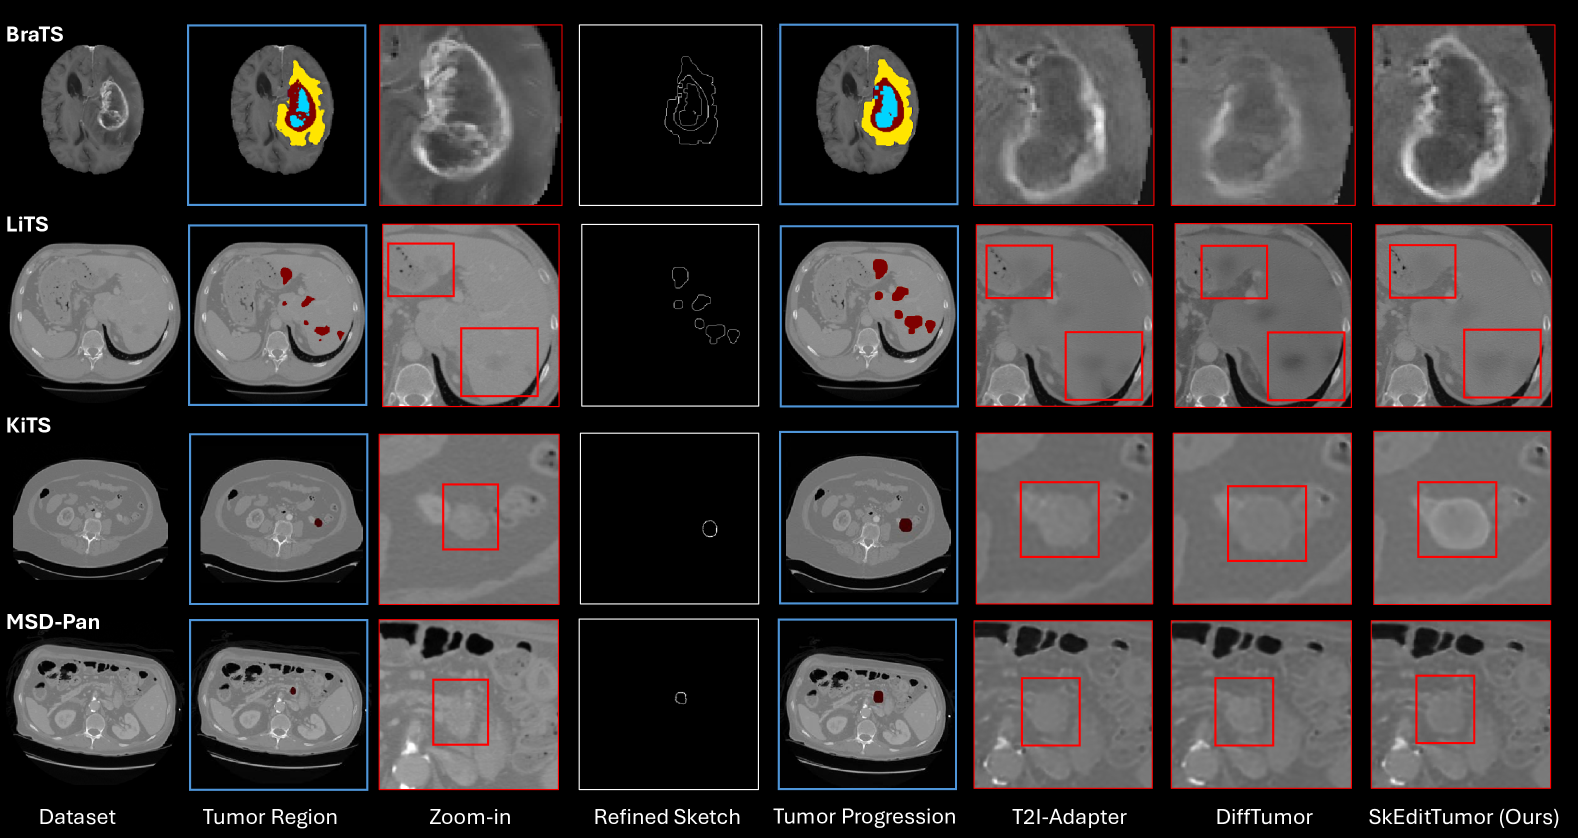

Figure 4: Tumor editing results across four datasets (BraTS, LiTS, KiTS, MSD-Pancreas). For each dataset, the input image, real tumor segmentation, and zoom-in view of the tumor region are shown, followed by the refined sketch and the corresponding segmentation for tumor expansion. The tumor editing results generated by T2I-Adapter, DiffTumor, and SkEditTumor (ours) are presented in the final three columns. The tumor regions (red boxes) highlight the differences in tumor structure preservation, with SkEditTumor producing more realistic and accurate edits compared to baseline methods.

We conducted a qualitative assessment of tumor editing—including reconstruction, progression, and regression—on the BraTS, LiTS, KiTS, and MSD-Pancreas datasets using T2I-Adapter, DiffTumor, and our proposed SkEditTumor framework. As illustrated in Fig. 4, SkEditTumor consistently demonstrates superior visual fidelity and morphological coherence across all datasets. In BraTS, T2I-Adapter and DiffTumor frequently produce tumor outlines that are either ambiguous or poorly aligned with the intended regions. In LiTS, DiffTumor’s edited tumors often display abnormally low HU intensities, diminishing radiological realism and pathophysiological plausibility. By contrast, SkEditTumor preserves anatomically relevant boundaries and yields more realistic intensities, effectively capturing subtle lesion characteristics. This advantage is especially evident in KiTS and MSD-Pancreas, where SkEditTumor produces clearer tumor margins and more distinct intratumoral structures. In comparison, T2I-Adapter and DiffTumor struggle with tumor expansion, resulting in blurred edges and reduced internal clarity. Overall, these findings underscore SkEditTumor’s robust editing capabilities and its effectiveness in delivering high-quality, anatomically coherent tumor modifications across diverse datasets.